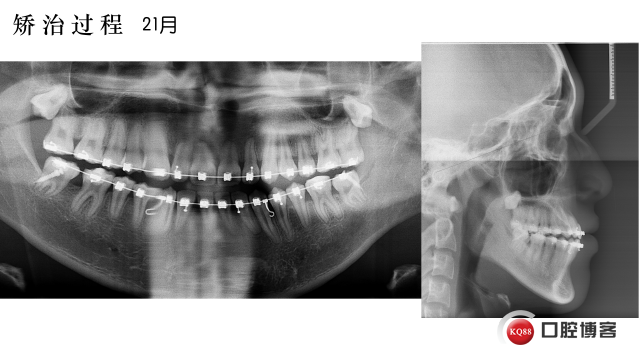

此病例其实早早就结束也做好幻灯,因为是投稿病例就迟迟未发出来,2017年4月投稿Ormco Forum没被选上,心想肯定石沉大海,又转投稿给2017年9月全国正畸年会,没想到双喜临门,8月初先被通知正畸年会的Ormco专场要上台做汇报,后宣布此病例进入年会全国前60强。